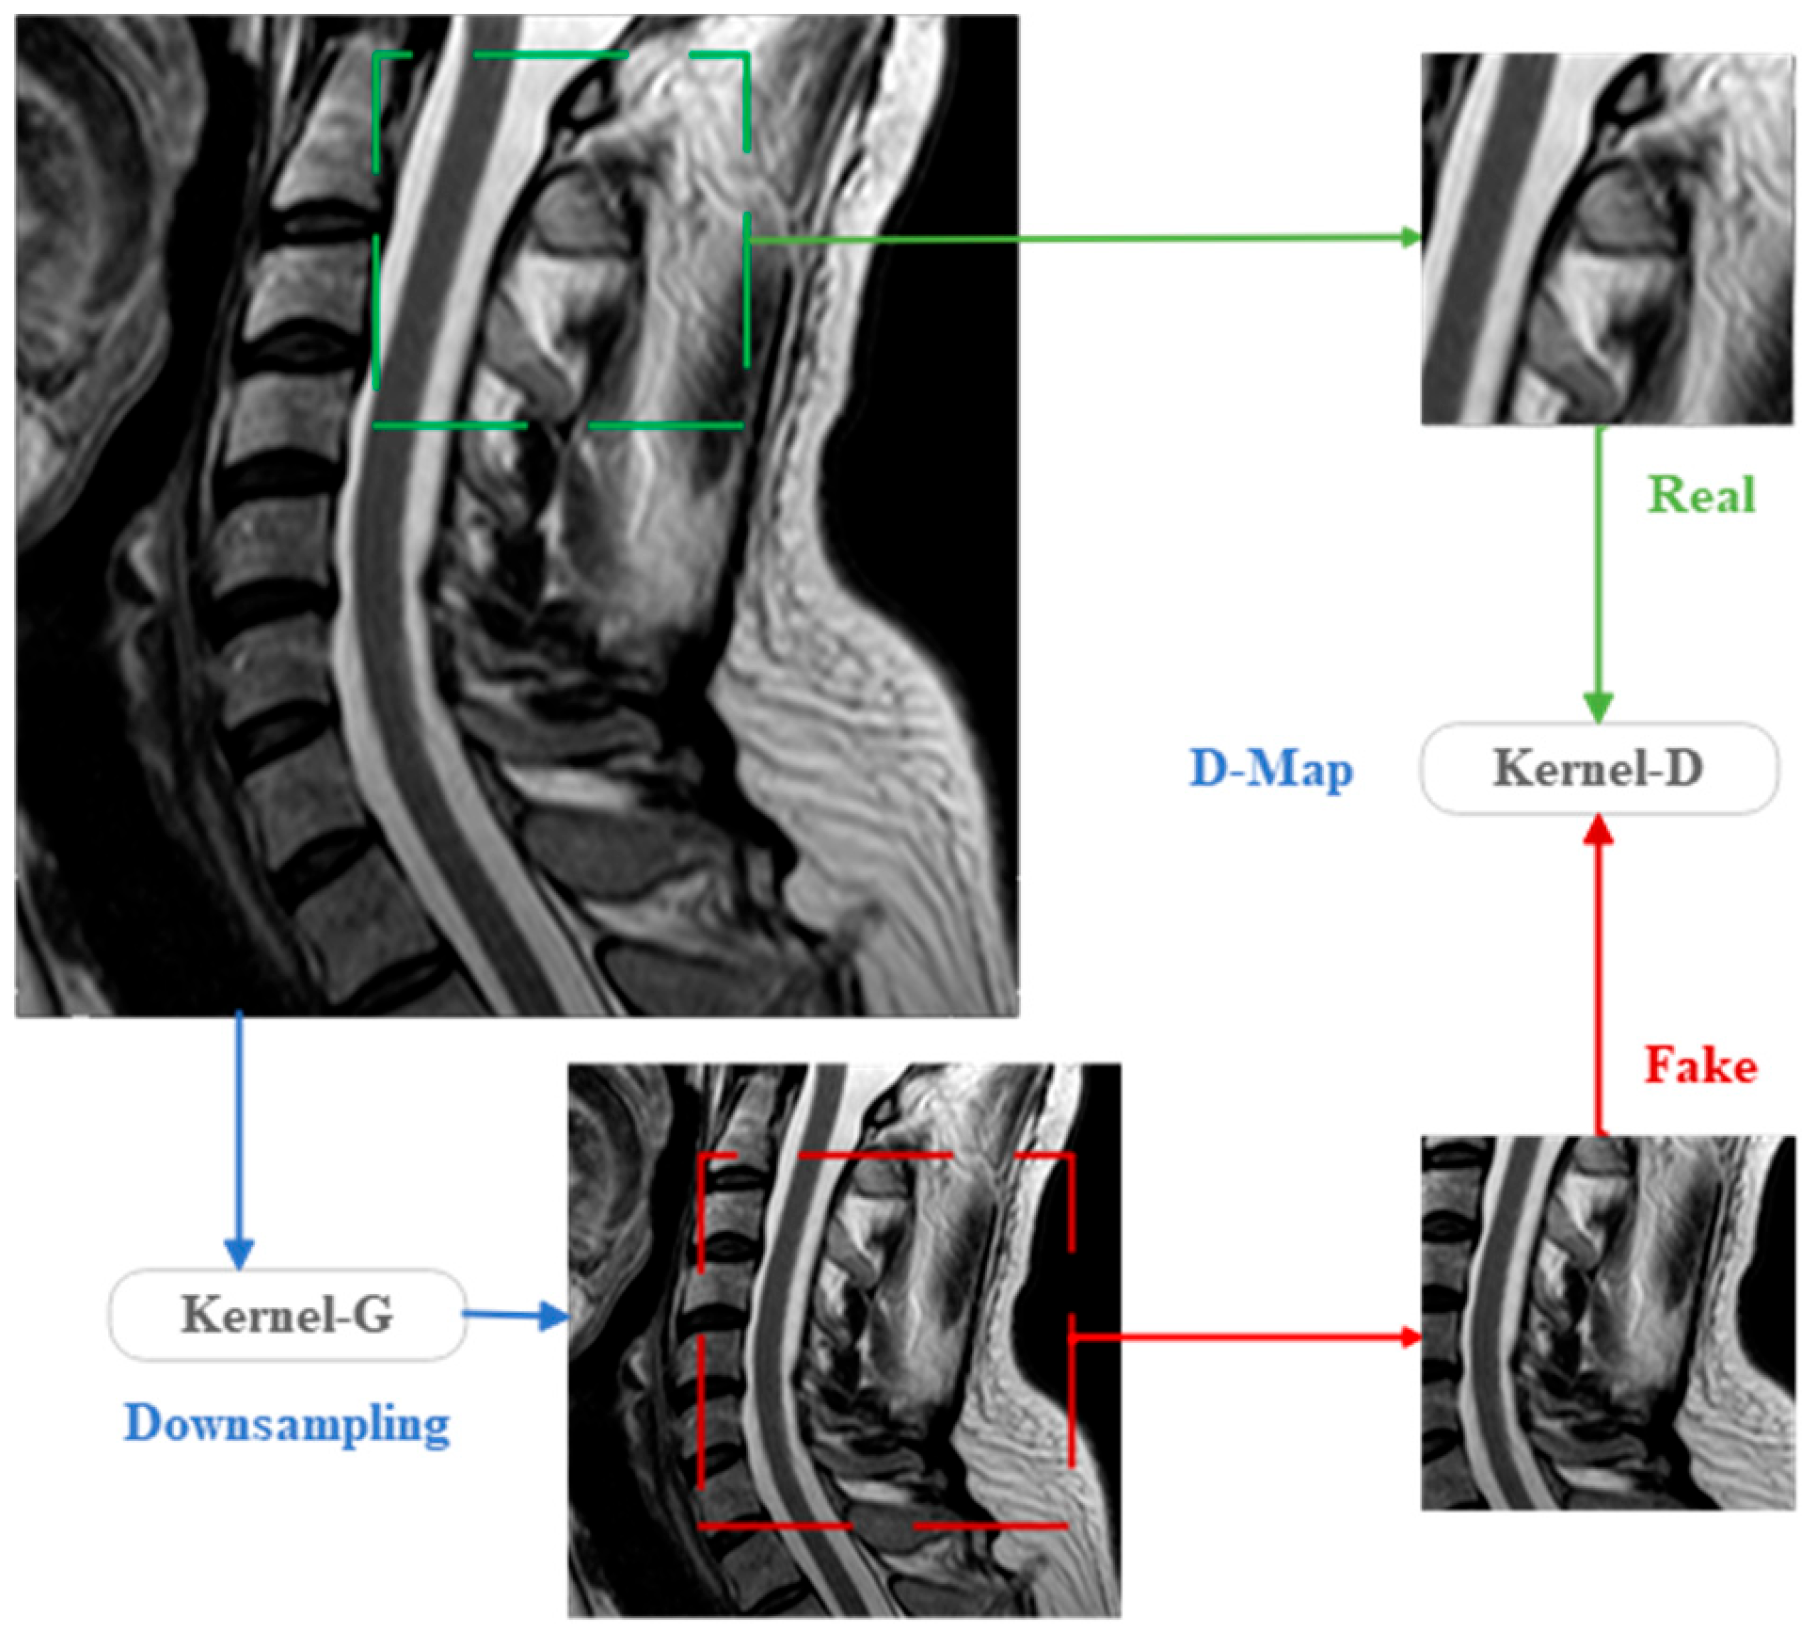

I SRC represents high-resolution raw images, while I LR represents low-resolution images generated by degradation. And k s and n are, respectively, denoted as the degradation kernel and degradation noise, while s signifies the scaling factor. The quality of both the degradation kernel and noise is intricately tied to the correlation between LR and HR image pairs, as well as with natural image pairs. Critically, it also exerts a profound influence on the precision of the extracted mapping features between LR and HR resolution images. Consequently, this quality factor plays a pivotal role in determining the quality of the ultimately generated SR images. Figure 2 offers a visual representation of the specific process by which LR images are derived from source images through the degradation mechanism.

I LR _ cl = I SRC k s

In this study, we employ KernelGAN for estimating image degradation kernels. KernelGAN is a blind super-resolution degradation kernel estimation model built upon the internal GAN framework, a fully unsupervised GAN that operates without requiring additional training data beyond the input image I SRC itself. KernelGAN solely relies on ISRC for training, learning the distribution of internal pixel patches within the image. Its primary objective is to identify the image-specific degradation kernel and search for the optimal kernel that preserves the pixel patch distribution across various scales of I SRC . Specifically, our goal is to “synthesize” a downsampled image so that its pixel patch distribution closely resembles that of the original I SRC . At the heart of this model lies the extraction of cross-scale recursive features between low-resolution (LR) and high-resolution (HR) images through deep learning, while the GAN component in KernelGAN functions as a potent tool for matching pixel patch distributions. Figure 3 illustrates the implementation process of KernelGAN where the model learns the internal pixel patch distribution of cropped patches through training on a single input image. It comprises a kernel generator (KGAN-G) and a kernel discriminator (KGAN-D), both fully convolutional, allowing them to operate on pixel patches rather than entire images, thus enhancing computational efficiency and feature extraction specificity. Given an input image I SRC , the kernel generator strives to learn the downsampling of I LR _ cl to a lower resolution, with the ultimate aim of deceiving the discriminator, rendering it incapable of distinguishing between the generated image and I SRC at the pixel patch level.

Figure 2. Flowchart Illustrating the process of degrading source images I src into LR images I LR .

Figure 3. KernelGAN structure.